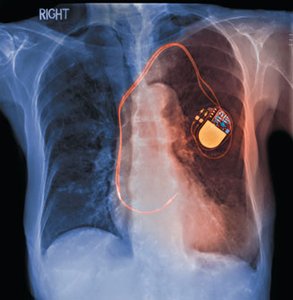

Timing circuits (e.g., windshield wipers, blinkers, pacemakers).

Medical devices such as pacemakers use RC circuits to control pulse timing.

Medical devices (e.g., pacemakers)